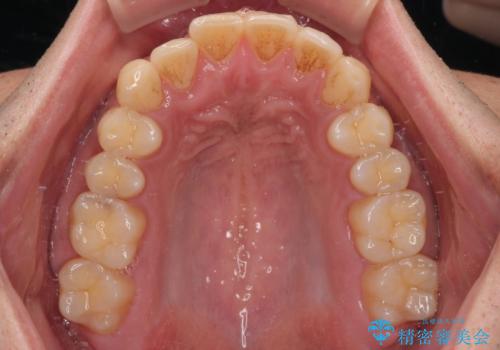

診察したところ、上下顎前歯部に軽度の叢生(ガタつき)が認められます。

目立たない装置を希望されたのでインビザライン ライトパッケージで治療を行うことになりました。